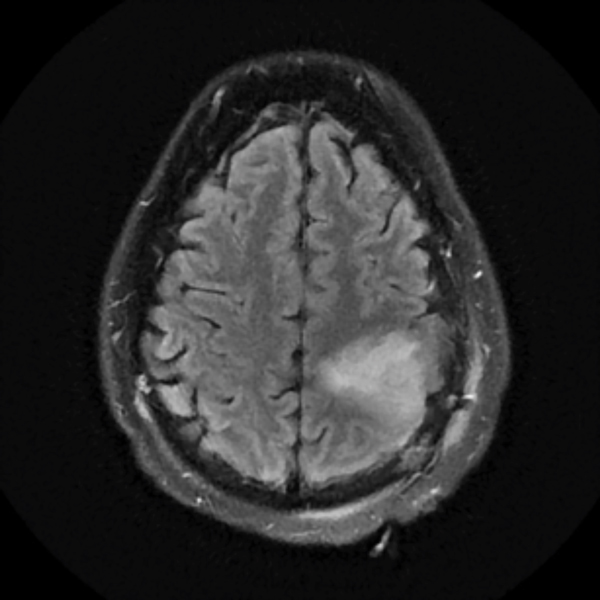

December 2019

A brain MRI showed an increased T2 signal in the left frontoparietal area. His tumor was non-enhancing. He underwent a partial resection of the tumor performed by NSPC neurosurgeon Ramin Rak, M.D., with intraoperative monitoring revealing eloquent motor cortex involvement anteriorly. The pathological diagnosis was WHO grade 2 oligodendroglioma.

Treatment with chemotherapy and radiation under the care of Dr. Grewal resulted in a durable response of the tumor as evident in the post-treatment images.